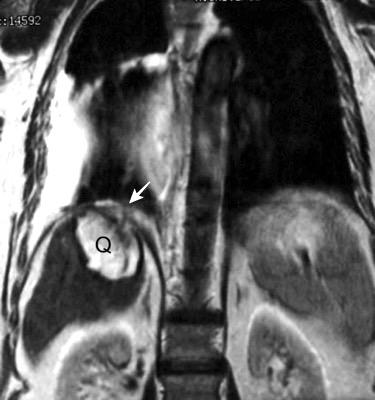

Quiste hidatídico.

Comunica con el hiato esofágico y el espacio pararrenal anterior.

Colecciones “inflamatorias” abdominales llegan al tórax vía el hiato esofágico o por vía transdiafragmática

Afectación transdiafragmática: 5,6-43,7% de quistes hepáticos. “Área desnuda” del hígado.

Panda A et al. “Straddling Across Boundaries”. Thoracoabdominal Lesions: Spectrum and Pattern Approach. Curr Probl Diagn Radiol. 2015 Área desnuda. El hígado en contacto directo con el tendón central del diafragma. Contiene el hiato de VCI.

Pedrosa I et al. Hydatid Disease: Radiologic and Pathologic Features and Complications. Radiographics 2000

Derrame pleural agudo. Migración transdiafragmática ocurre en 0,6-16% de casos. (área desnuda)